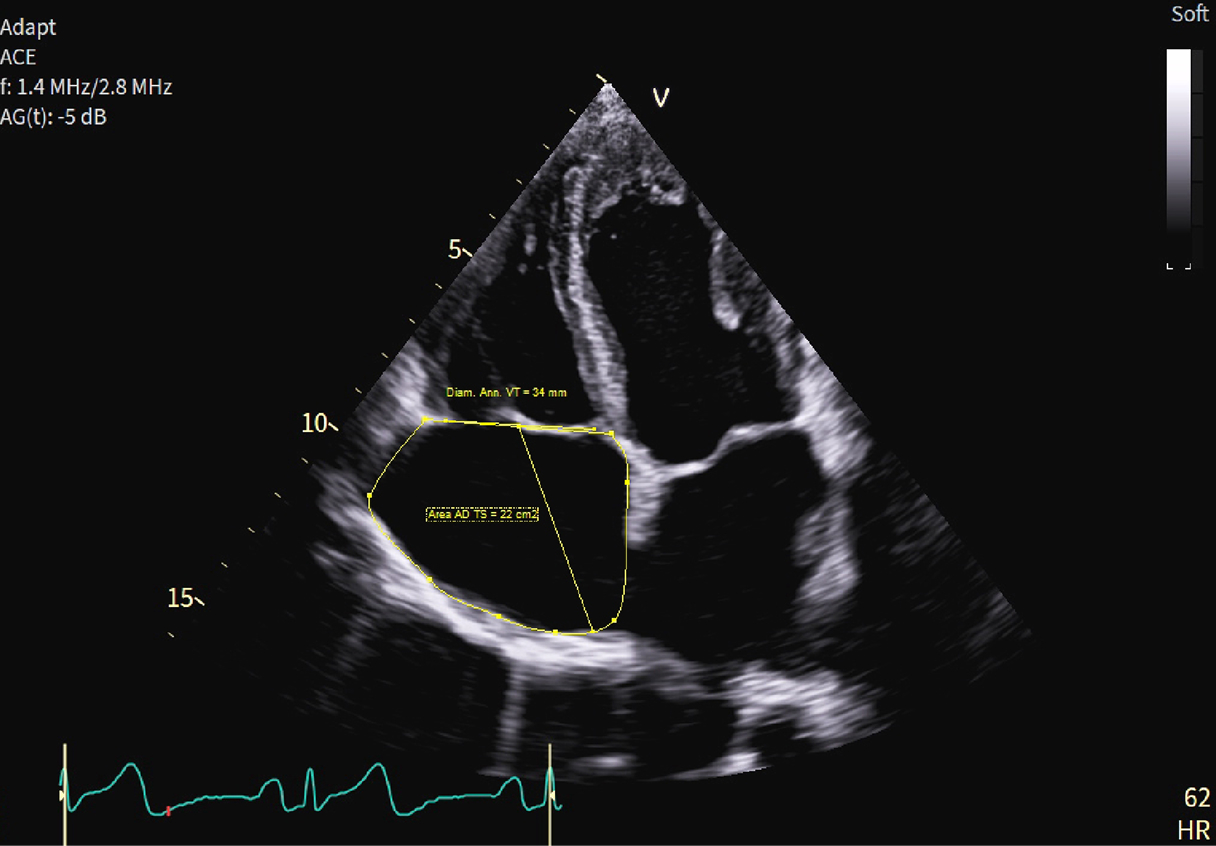

Dentro l'immagine

Fifty shades of grey

Caso condiviso da Marcello De Santis

Casi clinici

Scopri come le tecnologie di imaging più innovative di GE HealthCare hanno giocato un ruolo chiave nella diagnosi di condizioni cardiache complesse.